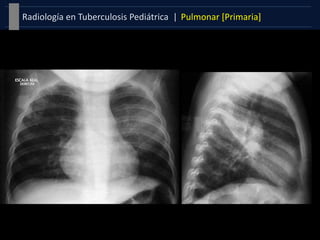

Patrón Adenopático

 El aumento con o sin

afectación parenquimatosa =

altamente sugestiva de Tb.

 Se encuentra en más del 90%

de los casos .

 Su localización suele ser hiliar o

mediastínica, con mayor

frecuencia unilateral.

 Patrón mas frecuente en

menores de 3 años.

Afectación parenquimatosa

Complejo primario [Ranke]

Foco de Ghon + linfangitis + Adenopatía

 Localizado en cualquier parte del

pulmón.

 No es habitual hallarlo con todos

sus componentes.

 Infiltración neumónica asociada

con adenopatías =Probable TB

 Atelectasia y Enfisema también

pueden estar presentes.

Formas Clínicas |Pulmonar [Primaria]Tuberculosis Pediátrica | Patrón Adenopático  El aumento con o sin afectación parenquimatosa = altamente sugestiva de Tb.  Se encuentra en más del 90% de los casos .  Su localización suele ser hiliar o mediastínica, con mayor frecuencia unilateral.  Patrón mas frecuente en menores de 3 años. Afectación parenquimatosa Complejo primario [Ranke] Foco de Ghon + linfangitis + Adenopatía  Localizado en cualquier parte del pulmón.  No es habitual hallarlo con todos sus componentes.  Infiltración neumónica asociada con adenopatías =Probable TB  Atelectasia y Enfisema también pueden estar presentes.